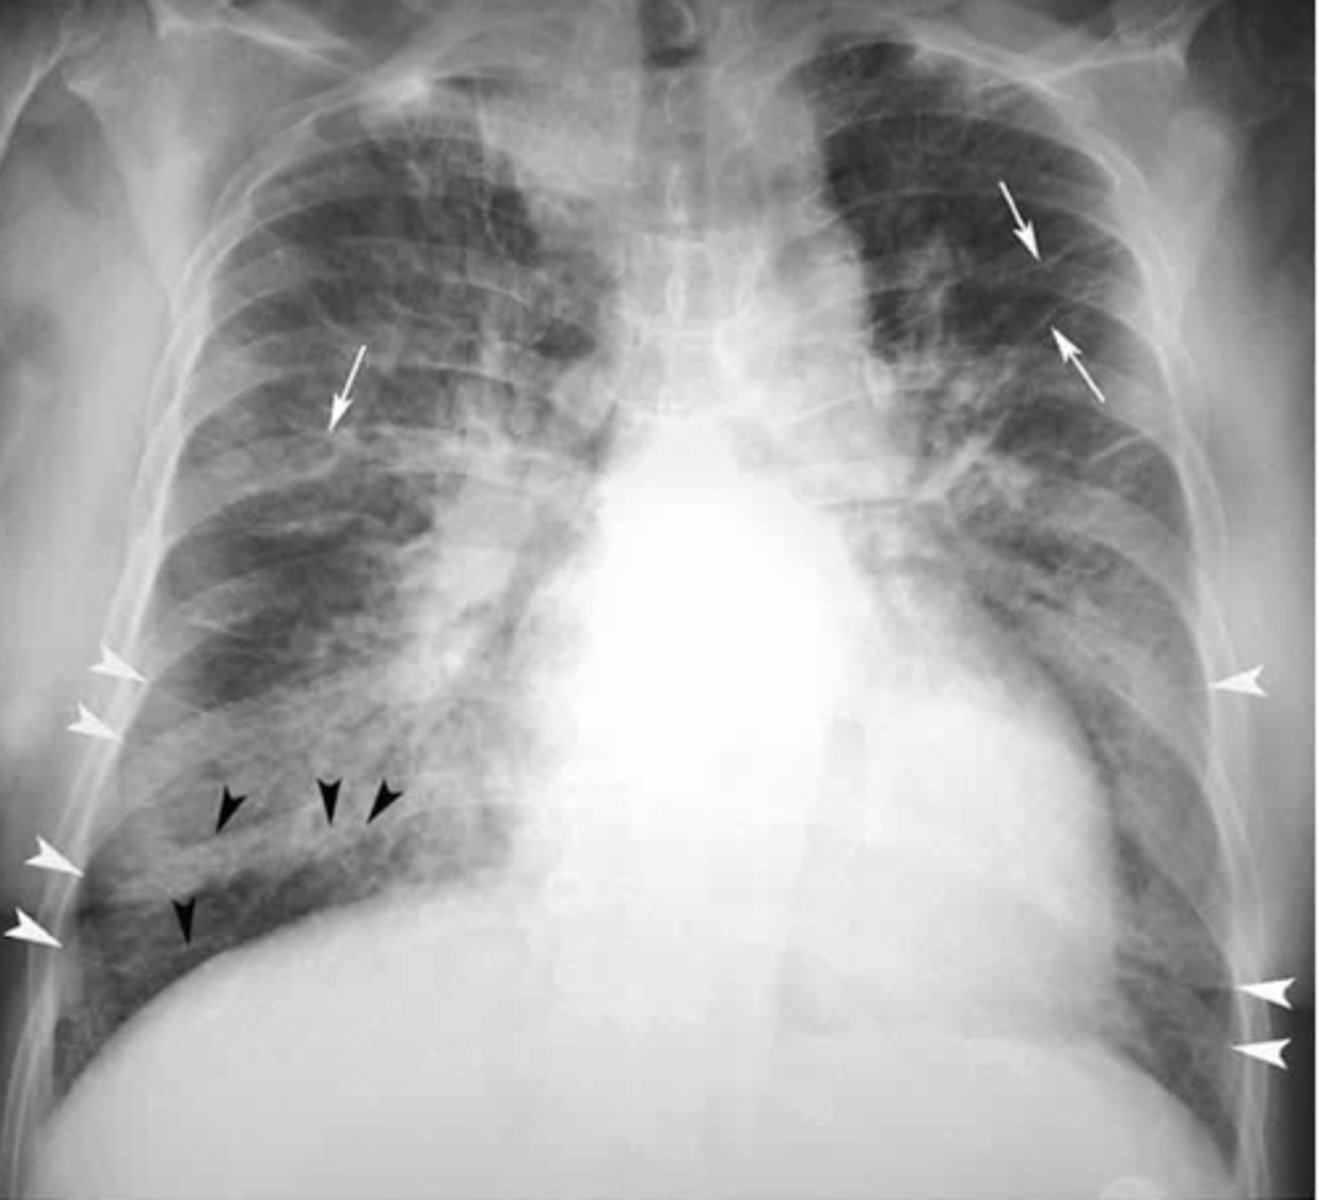

Mild to moderate CHF with redistribution of pulmonary vasculature, indistinct hila, mild cardiomegaly and Kerley B lines.

What signs on radiograph indicate CHF?

<p>What signs on radiograph indicate CHF?</p>